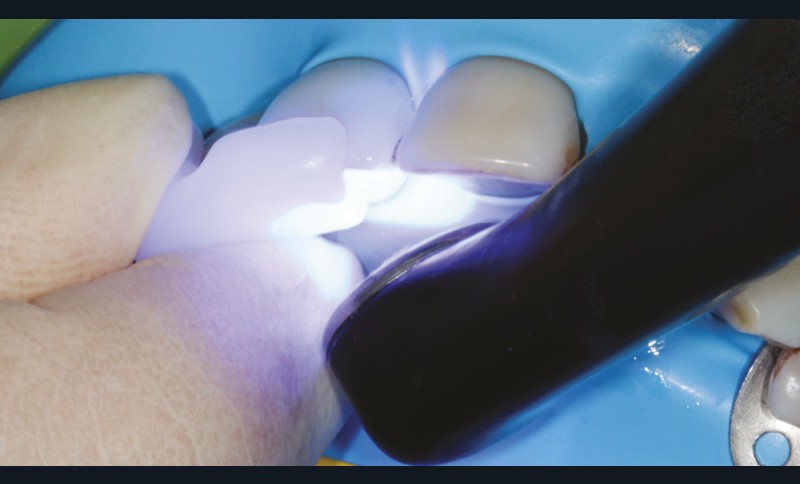

L’assemblage se fait au moyen de la colle Panavia V5 (Kuraray Noritake). Le bridge est positionné grâce à la clef « papillon » rigide. Les excès de ciment sont retirés de façon rigoureuse à l’aide d’un micro-applicateur et la colle est photopolymérisée 20 secondes par face (fig. 25).

Une couche de glycérine est appliquée sur la périphérie de l’ailette lors de la photopolymérisation finale. L’occlusion est scrupuleusement corrigée en statique et en dynamique puis l’ensemble est finalisé à l’aide de polissoirs (fig. 26).